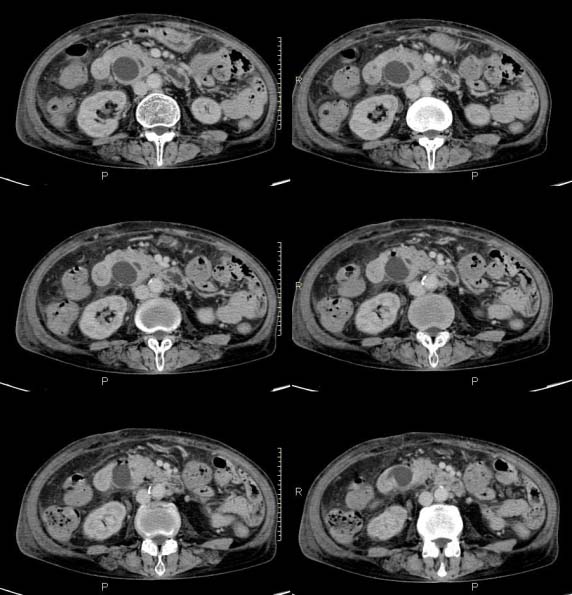

女,71岁,腹痛、腹胀、黄疸20余天,b超示肝内外胆管高度扩张内伴絮状物质(未提示梗阻部位或结石影),经抗炎解痉治疗后,肝功能有所好转,但胆道梗阻状态并未减轻。患者曾于1970年代做过胆囊切除术,1997年因胰腺炎而手术;且患者有糖尿病10余年。ct图片传了静脉期,未传动脉期了,最后一序列为3.2mm薄扫,请各位同仁仔细看看,确定一下胆管梗阻的部位,是炎性梗阻还是肿瘤性梗阻,是否与胰腺炎有关系,扩张胆总管中段前缘是否是胰管。请高手们最好用图示来指出梗阻部位。

请大家看看扩张的胆总管内见一弧线形间隔,怎样解释?

肝内外胆管显著扩张,考虑先天性胆管囊肿(ⅳ型)。

肝内胆管远侧、近侧不比例扩张,以近侧为明显。胆总管扩张。考虑先天性胆管囊肿(ⅳ型)。